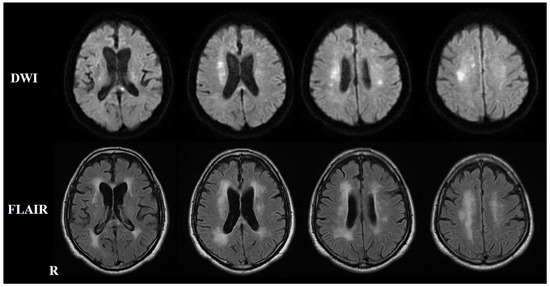

2. Case Presentation